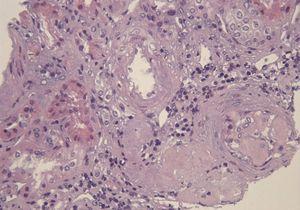

A 29-year-old man of southern Italian ancestry, was admitted to the hospital. Since the first months of life he had experienced characteristic febrile attacks associated with sore throat, myalgias, vomiting and diarrhoea. Later the attacks of fever reduced their frequency but in the last year there was an increased frequency of febrile episodes with proteinuria in nephrotic range. On admission his blood pressure was 150/80mmHg and temperature 36.5°C. Heart sounds were clear with regular sinus rhythm and pulse rate was 88 beats/min. Physical examination showed normal findings and no symptoms suggestive of respiratory, abdominal or urinary infection were apparent. Chest radiography and abdominal ultrasonography scan revealed no abnormalities. Laboratory investigations showed proteinuria 9.17g/day, a raised erythrocyte sedimentation rate, a normal C-reactive protein, a total leukocyte count of 12.500/mm3, serum amyloid 3.67mg/L, serum IgD 233UI/ml (normal range 0-100), creatinine 1.09mg/dl. Immunological tests and other laboratory parameters resulted negative or within normal limits. Kidney biopsy: among 28 glomeruli, 18 showed a weakly eosinophilic amorphous material infiltrating the mesangium (Figure 1 and Figure 2). After positive Congo red staining, the deposits revealed apple-green birefringence under polarized light, consistent with the presence of amyloid. On immunochemistry, the amyloid deposits were negative for antibodies against kappa and lambda chains (Figure 3). Clinical and laboratory findings suggested diagnosis of systemic reactive amyloidosis. The research for MEFV, for Familial Mediterranean Fever (FMF) and TNFRSF1A, for Tumor Necrosis Factor Receptor-Associated Periodic Syndrome (TRAPS) mutations was negative; the research for 2 mevalonate kinase (MVK) mutations was positive in heterozygosis, diagnosing the HIDS. The patient started therapy with Anakinra, Interleukin -1 antagonist.

Figure 2. Kidney biopsy